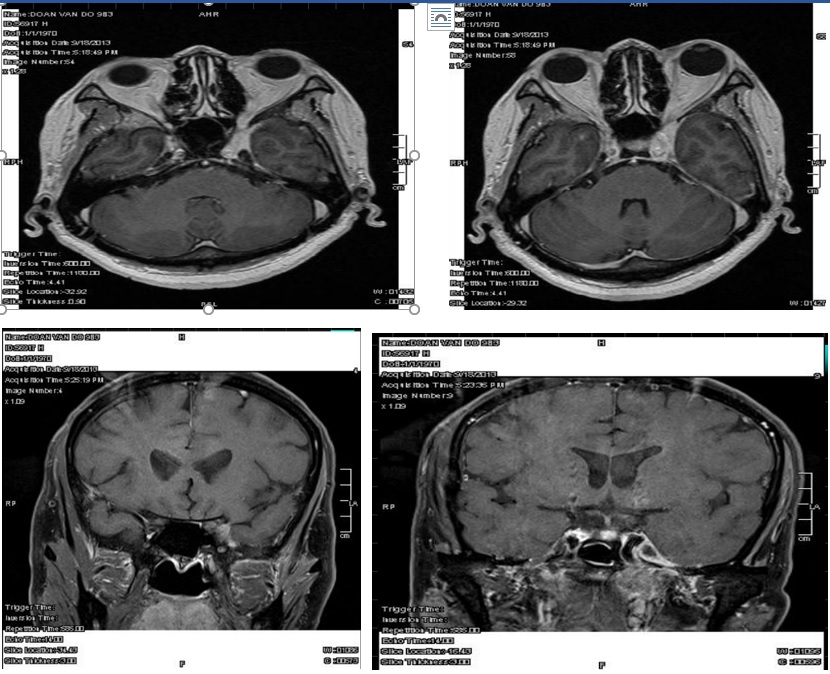

MRI xoang hang

22/10 (lần nhập viện trước): Ổ tổn thương vùng xoang hang (T) lan vào khe ổ mắt trên và hốc mắt phía dưới (T) nghĩ viêm – 19/11: t/d u thành sau mũi hầu (T), xâm lấn xoang hang (T), đỉnh ổ mắt (T) (?)

Chẩn đoán xác định: U thành sau mũi hầu (T) xâm lấn xoang hang (T), khe hốc mắt trên (T)